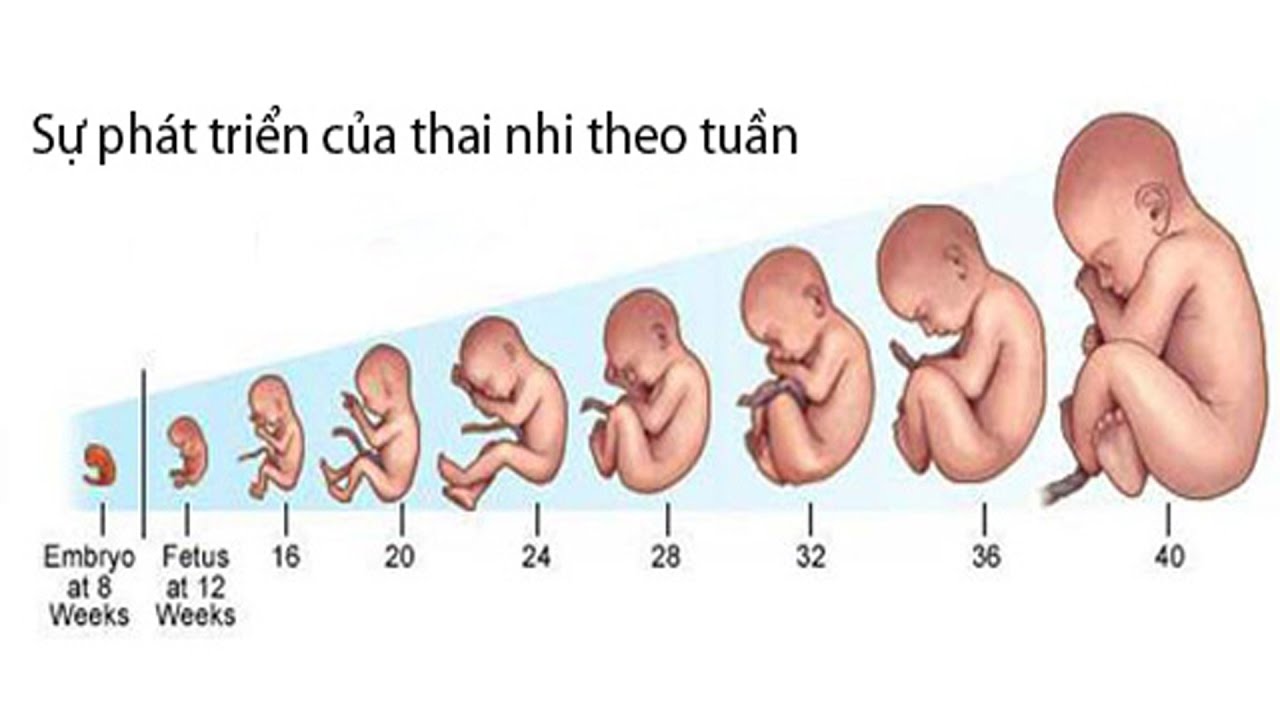

Эмбриональный период: Развитие эмбриона от зачатия до рождения